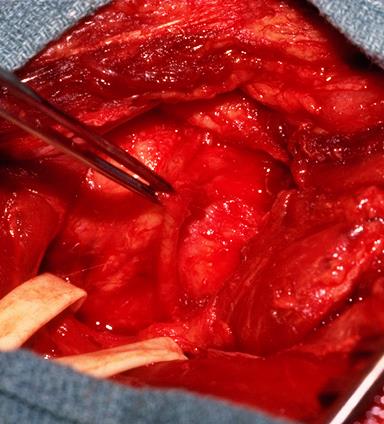

Open posterior capsular plication

Technique

AO surgical foundation posterior approach glenoid / scapula

Lateral Position

- vertical incision over glenohumeral joint

- elevate deltoid or split deltoid

- interval: between supraspinatus and infraspinatus

- interval: between infraspinaus and teres minor

- can detach infraspinatus tendon and elevate off capsule

- suprascapular nerve 1.5cm medial to glenoid

- axillary nerve below teres minor

- perform capsular plication / capsular shift

- +/- lateral advancement of infraspinatus

Identify and elevate deltoid / detach from scapular spine / identify infraspinatus

Identify interval between infraspinatus and teres minor, detach and reflect infraspinatus to expose posterior capsule and glenoid